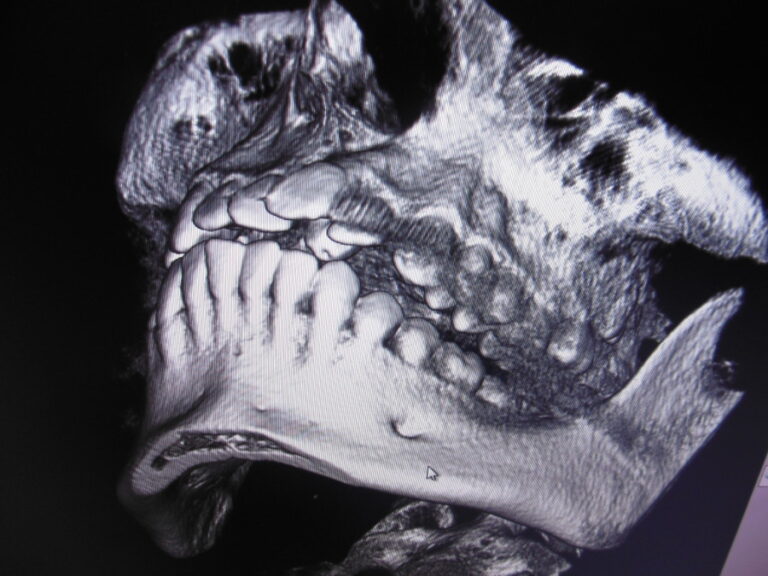

Ortodoncja CBCT

Leczenie chirurgiczno-ortodontyczne wad zębowych z zastosowaniem tomografii spiralnej CBCT w naszej klinice.